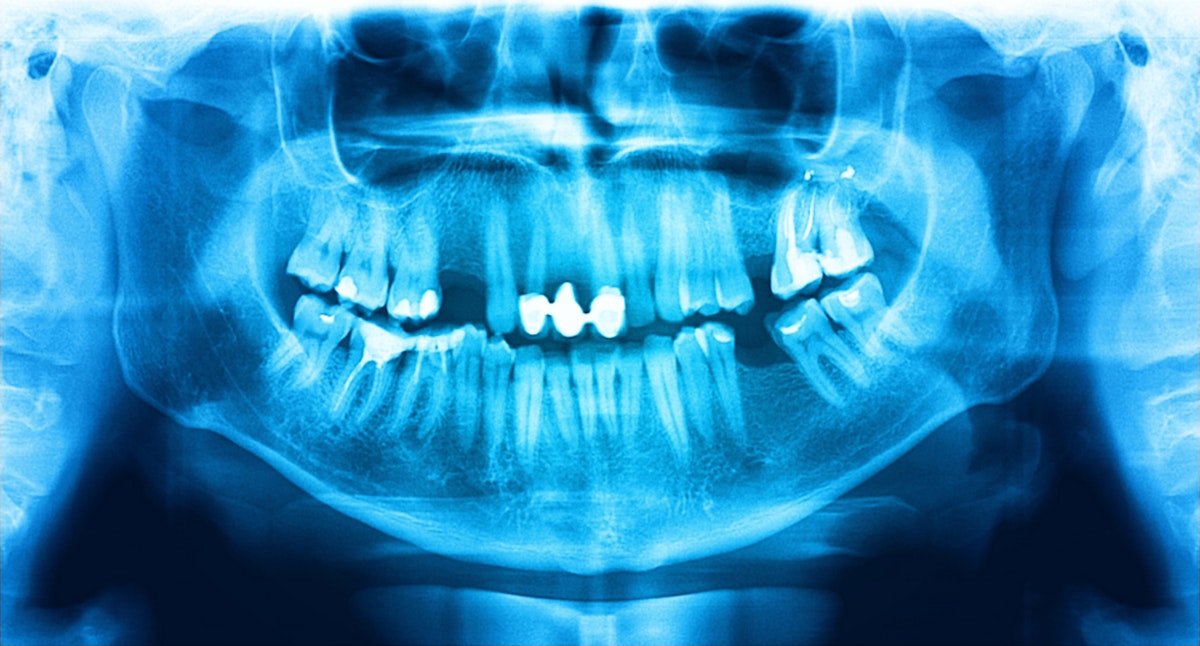

Are you aware of x-ray equipment licensing requirements?

Although practitioners no longer have to pay an annual licence fee (provided they have APC and appropriate scope) there is now a source licence fee for each site where x-ray equipment is owned or controlled.